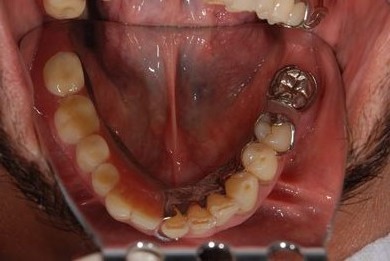

骨再生スピードインプラント治療+遊離歯肉移植

| 治療内容 | インプラント8本(サイナスリフト、抜歯即日スピードインプラント)、ハイブリッドセラミッククラウン9本、遊離歯肉移植 | ||||||||||||||||||||||||||||||||